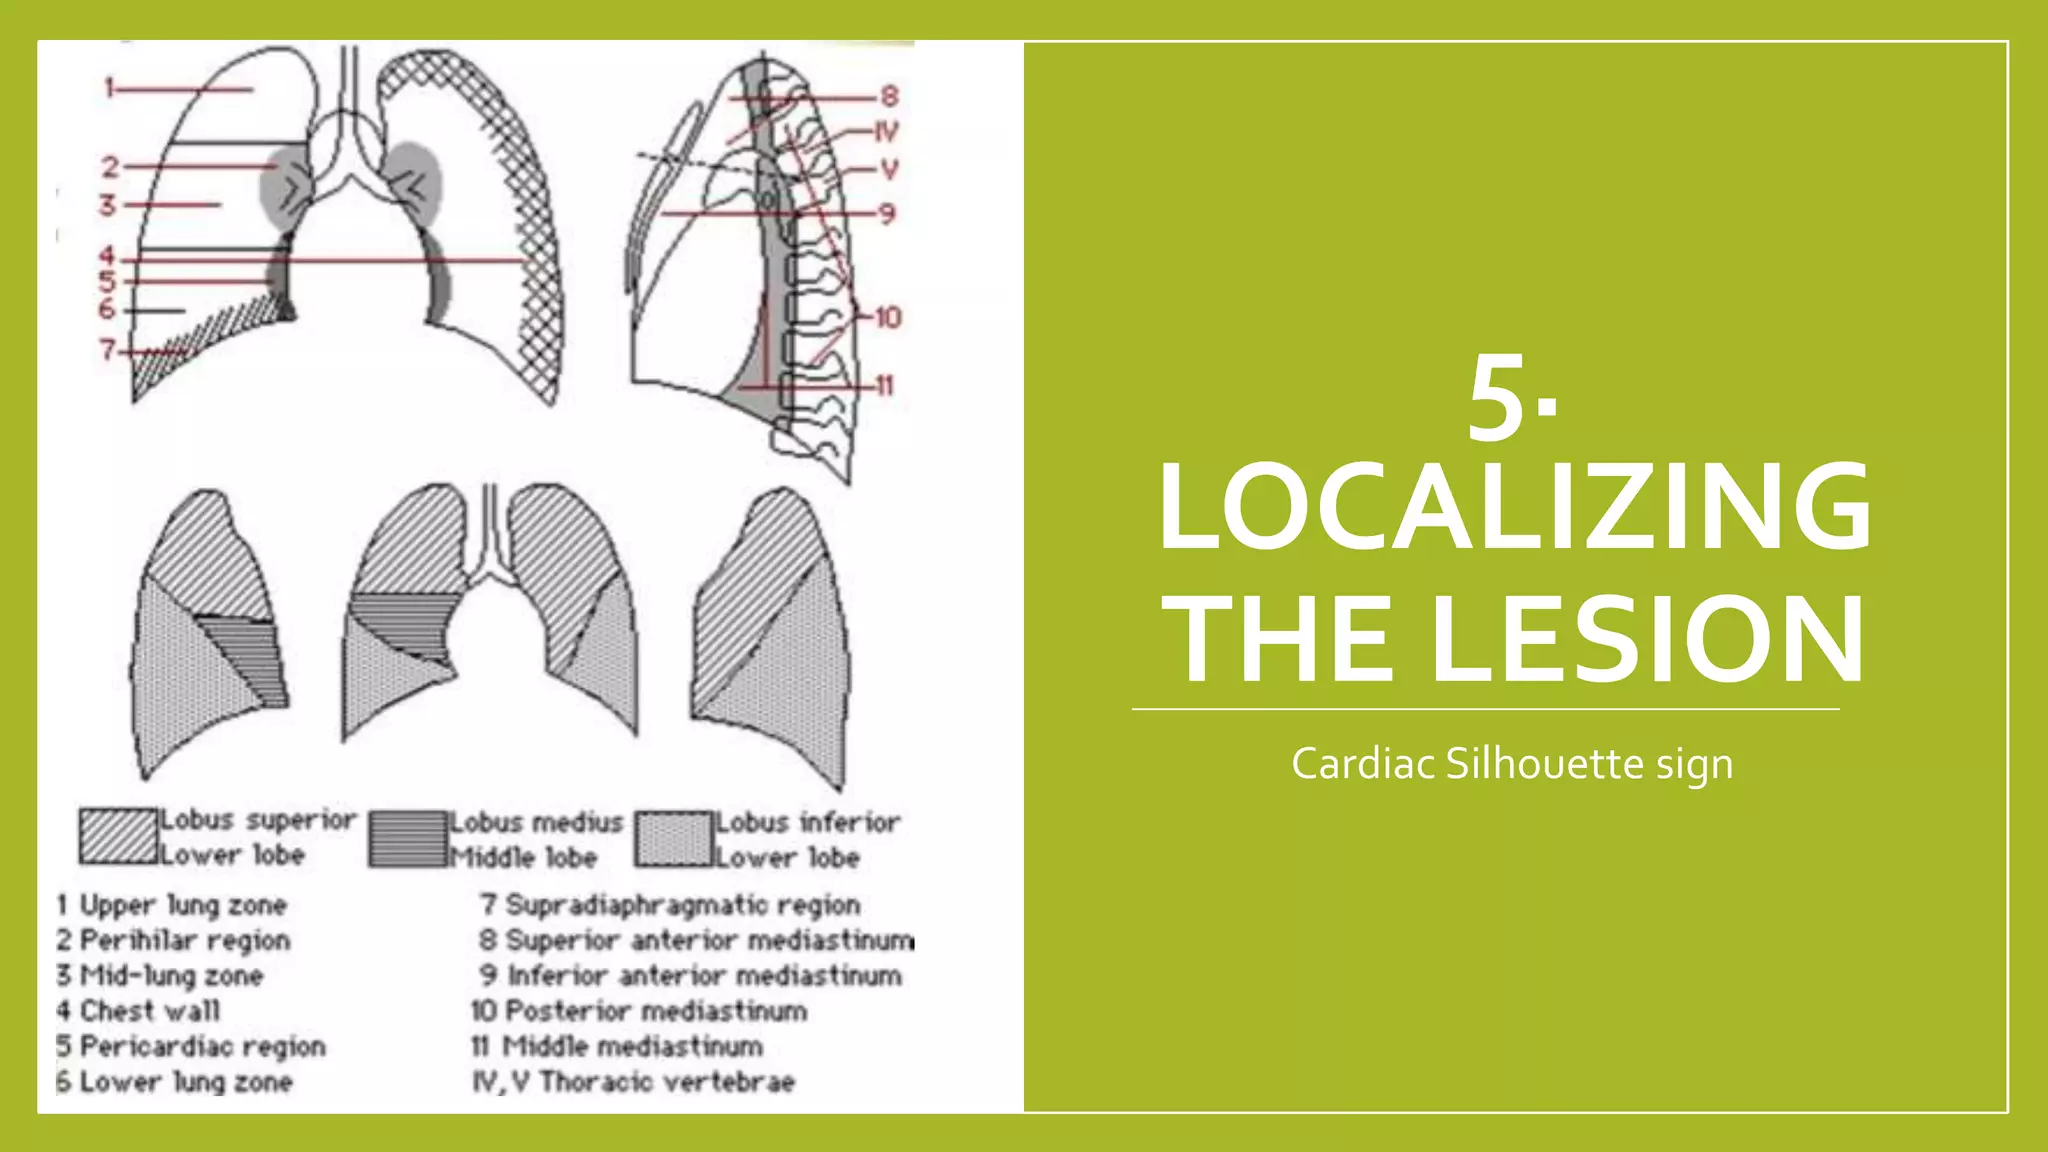

The document provides guidance on approaching and interpreting chest x-rays (CXR). It outlines steps to check the name, date and quality of the film, systematically scan the CXR looking for abnormalities, and determine if the lungs appear too white or black. Specific signs are described to help localize abnormalities, including the cardiac silhouette sign and pleural effusion signs. Examples are given of respiratory distress syndrome, tetralogy of fallot, transposition of great arteries, and total anomalous pulmonary venous return. The take home message is to summarize positive findings, compare to prior CXRs if available, and confirm findings with a radiologist.